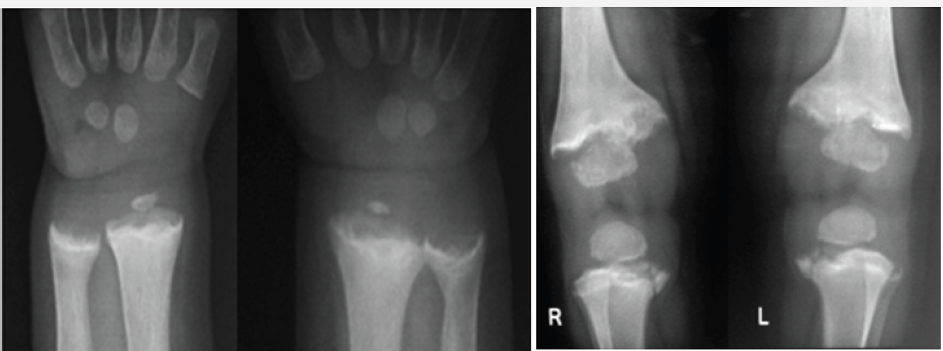

Figure 2 a & b: 2 M Rickets, a- clinical, b- radiograph of pelvis.

Figure 2 c& d: 1 1/2yrs, Rickets, a- hands, b- knees.

In young children and adolescents, characteristic radiological appearances are noted on conventional films. These include osteoporosis, metaphyseal cupping and ground glass appearance of growing and weight bearing bones (Figure 2a-2d). Rachitic rosary deformity is common in the chest with cupping of the costochondral junctions (Figure 2e & 2f).